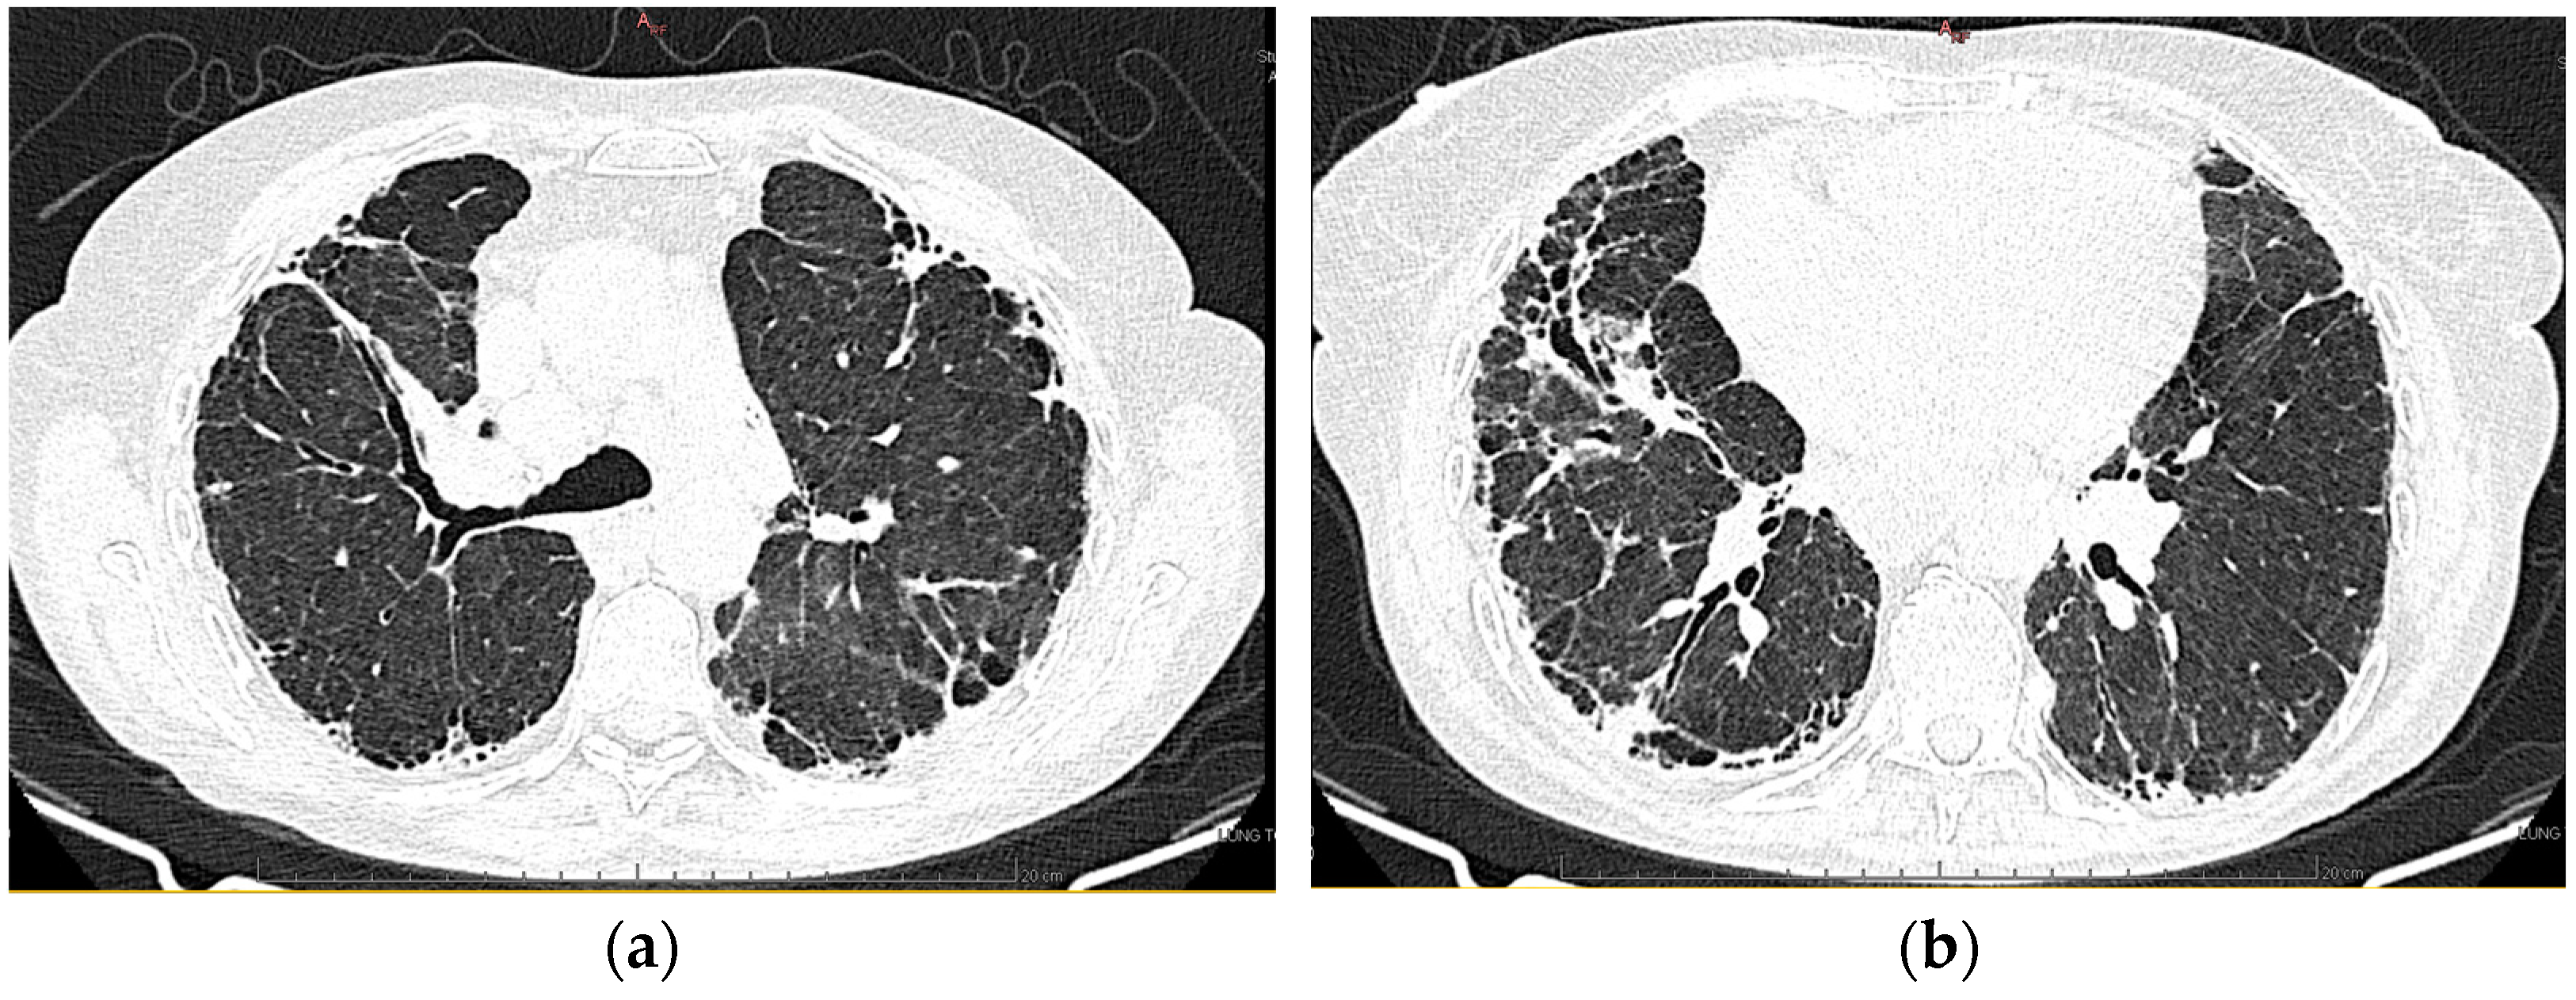

2.1.10. High-Resolution Computed Tomography (March First 2023) (Figure 3)

Predominantly subpleural reticular lesions, with a four-cornered appearance, associated with minimal right anterobasal peribronchovascular extension. Traction bronchiectasis is associated with the reticular beaches above. Subpleural areas of honeycombing are more accentuated in the lower half of the lung. Discrete peripheral organizing masses, especially in the left posterior. Fibrous bands with small associated calcifications. The pleural contour is irregularly marked, with numerous spicules on the contour. The esophagus is markedly dilated along its entire length, with a caliber of up to 26 mm, regular walls, and liquid stasis in the lower half. Circumferential pericarditis in a small amount. Global cardiomegaly. The pulmonary artery cone has a caliber of 36 mm, in the context of known pulmonary hypertension. Numerous supracarinal bilateral mediastino-hilar adenopathies, some of them with small calcifications, with an inflammatory appearance. Thyroid with normal position and dimensions, inhomogeneous, micropolynodular structure. Conclusions: The CT appearance is an appearance of interstitial lung pneumopathy: progressive fibrosing phenotype, examination quasi-identical to the previous CT examination. Dilated pulmonary arteries with the appearance of PAH. Minimal pericarditis. Cardiomegaly. Polynodular goiter. Dorsal spondylarthrosis.

Figure 3.

(a,b): Reevaluation of lung tomography.

Considering the underlying pathology, progressive systemic sclerosis and interstitial lung disease, the next step in the diagnostic process was progressive evaluation. The restrictive pattern expressed on the body plethysmography associated with a significant decrease in DLCO, the clinical deterioration of the patient, and the progression of imaging lesions on HRCT led to the classification of the patient as having an SSC-ILD progressive phenotype.